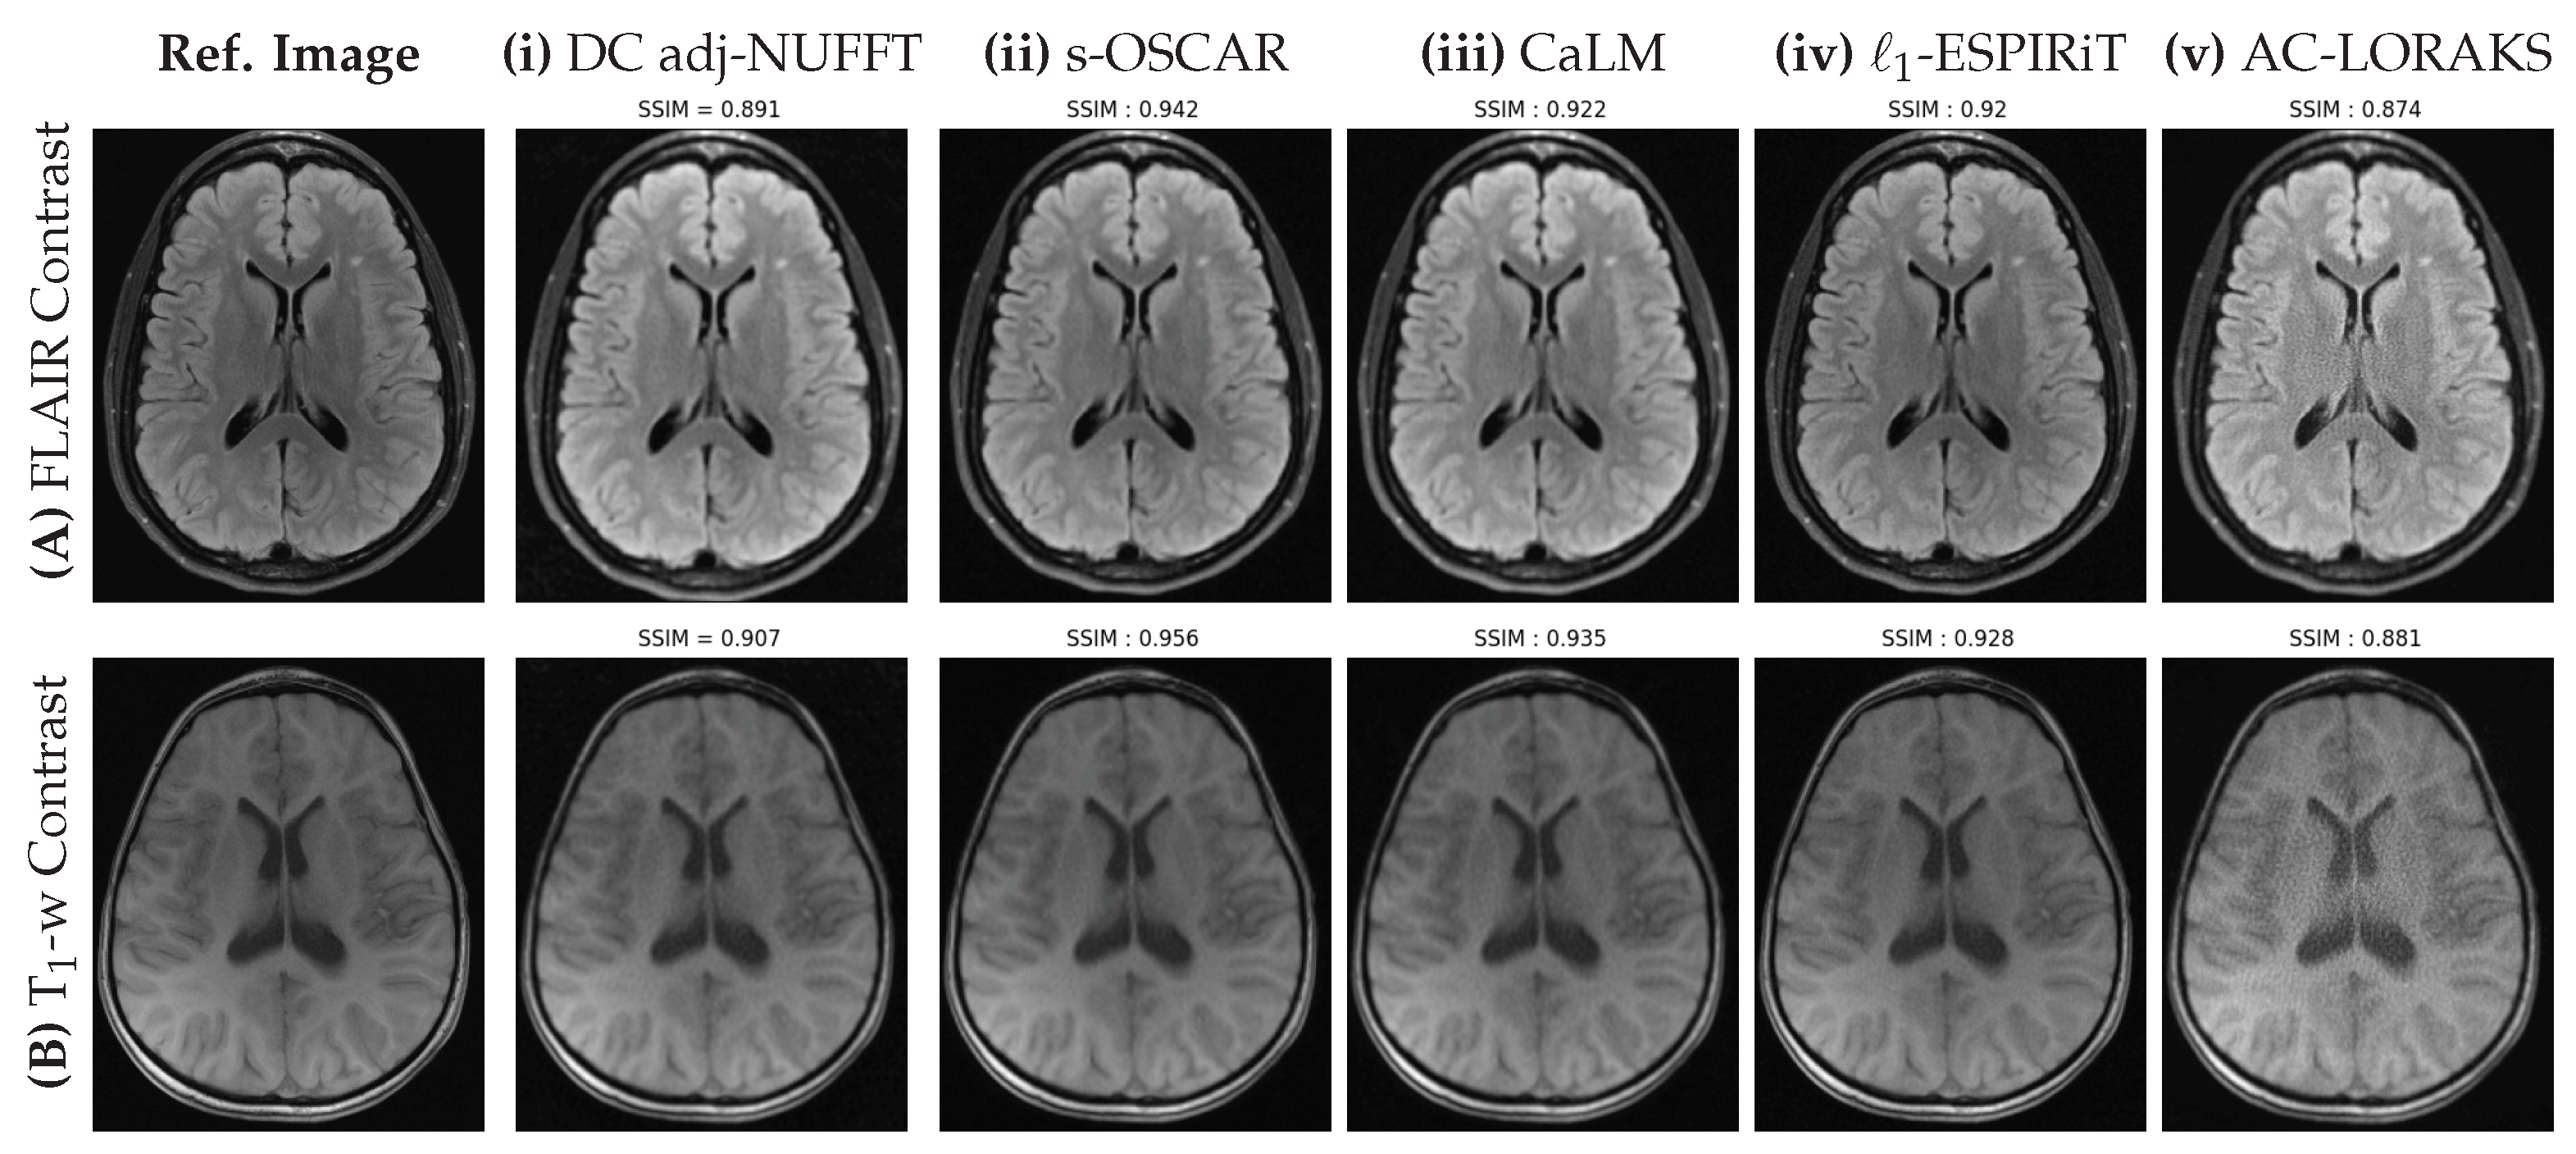

5.2. Prospective Studies